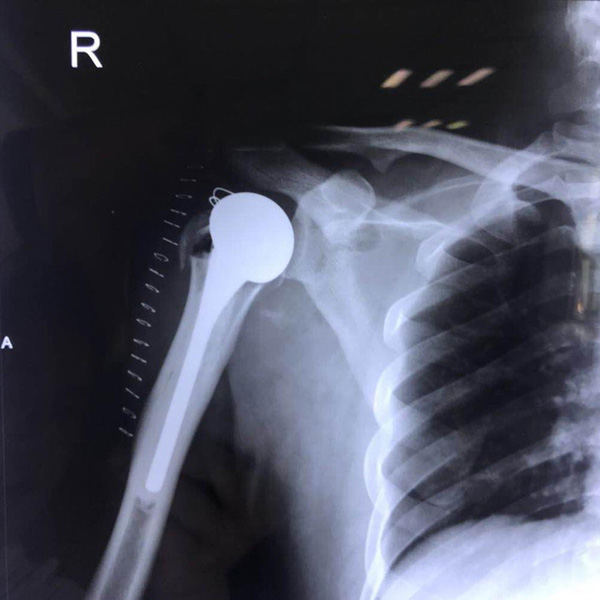

• 右側肱骨頭置換右側肱骨頭置換手術后手術前

右側肱骨頭置換

患者郭某,男,40歲,因嚴重車禍導致“右肱骨頭粉碎性骨折”,一般的手術很難將粉碎的骨折塊拼接起來,即便大致的拼接起來,因為骨面的不平......